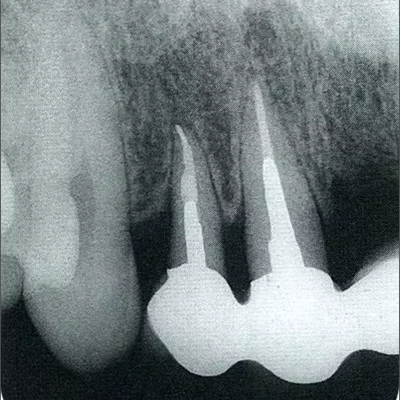

深牙周袋的治療

圖10-10  術后2年的x片。確認骨水平獲得改善,牙周探診值在2mm以下